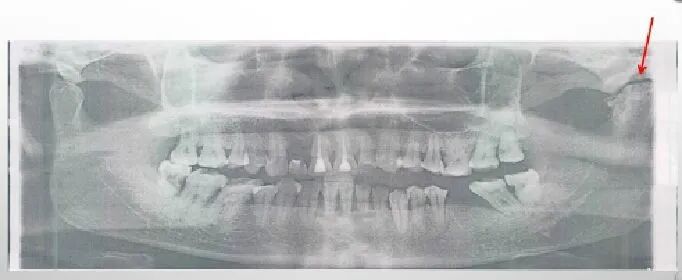

1) 优点:显示上下颌骨全貌:颌骨形态、牙齿发育、全口牙周病牙槽骨吸收情况、颌骨病变及骨折等。

2) 下颌骨特点:把马蹄弓形的上下颌骨展为平片;骨皮质厚薄不一但光滑连续(对比骨折);骨松质纹理水平;髁突形态多样;下牙槽神经管的特点(分叉位臵多样)。

拍摄全口牙齿,二维成像 ,便于医生快速、全面的掌握患者牙齿情况,如儿童牙齿发育情况(根尖闭合情况等)、成人牙周情况。

①颏孔 ②下颌管 ③髁突 ④喙突 ⑤舌骨 ⑥上颌窦底 ⑦硬腭 ⑧鼻腔 ⑨眼窝 ⑩颧弓

正畸前拍摄全景片,检查患者牙体、牙髓、牙周、关节等情况,可以帮助正畸医生更好的把握患者正畸前情况,合理制定方案,对于全景片无法清晰显示的位置,可以再通过拍摄cbct或者单牙位片的方式进行诊断。原则是尽可能在正畸前完成全面的检查并记录,既是对患者负责,又是对我们方案、治疗过程的有效信息的掌握。避免纠纷和风险。你懂~~~~~